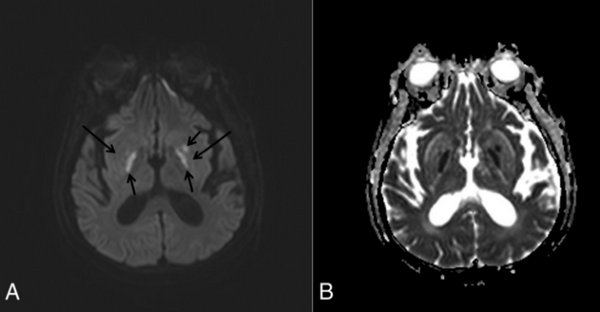

DWI-изображение (А) и ADC-карта (В) иллюстрируют нормальный сигнал (длинные стрелки) с ограниченной диффузией на DWI (короткие стрелки) в обоих базальных ганглиях и левой скорлупе с наличием зон цитотоксического отека в очагах поражения.

На T2-WI изображении (А) определяются типичные «вилкообразные» изменения в базальных ганглиях билатерально. Шесть месяцев спустя на T2-WI изображении (В) видно полное разрешение очагов поражения.